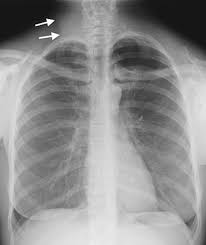

Abstract pneumothorax is the most urgent cause of a hyperlucent thorax. The radiographic finding that a lung or portion thereof is less dense than normal as from air trapping by a bronchial foreign body asymmetric emphysema or decreasing blood flow. Emphysema causes both over inflation and decreased pulmonary vasculature. Asymmetrical distance between the medial.

An x ray simply is fundamentally useless to properly diagnose your problem. A rotated posterior anterior view may result in artifactual decreased attenuation on the side rotated anteriorly because of a shorter distance between the patient and the incident x ray beam. Hyperlucency imaging a region on a plain film with tissue density allowing for transmission of x rays. Initial interpretation should include excluding pseudo causes of hyperlucency because of technical factors.

Spirometery of the patient was within normal limits. The most common causes of pulmonary hyperlucency in adults are summarized in figure 1. Hyperlucent lungs result from air trapping or decreased pulmonary vasculature. Unilateral hyperlucent lung.

Contrast enhanced computed tomograph cect of the chest showed an unremarkable lung fields and vasculature. An understanding of the broad differential di agnosis of pulmonary hyperlucency is necessary to determine the underlying cause and provide appropriate patient care. Every unnecessary x ray in a woman of child bearing age represents a danger that should be weighed against the benefits. What does lung hyperlucent mean.